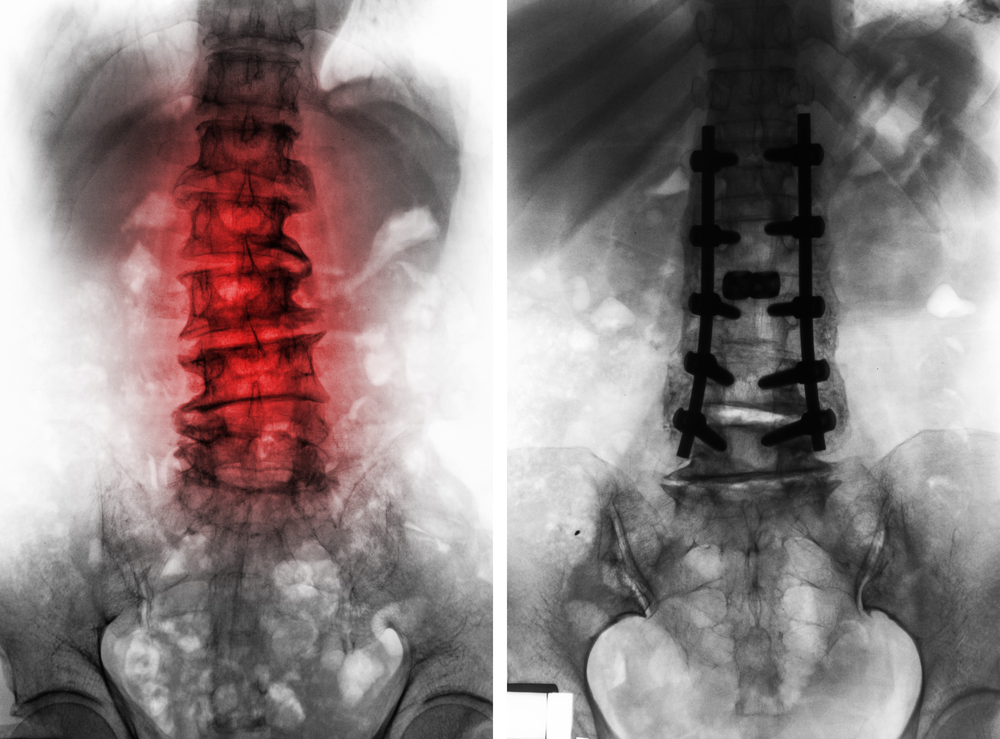

Side-by-side spinal X-rays: the left image shows a lumbar spine with red highlights indicating inflammation and disc degeneration; the right image shows a lumbar spine after surgery with metal rods and screws for spinal fusion.